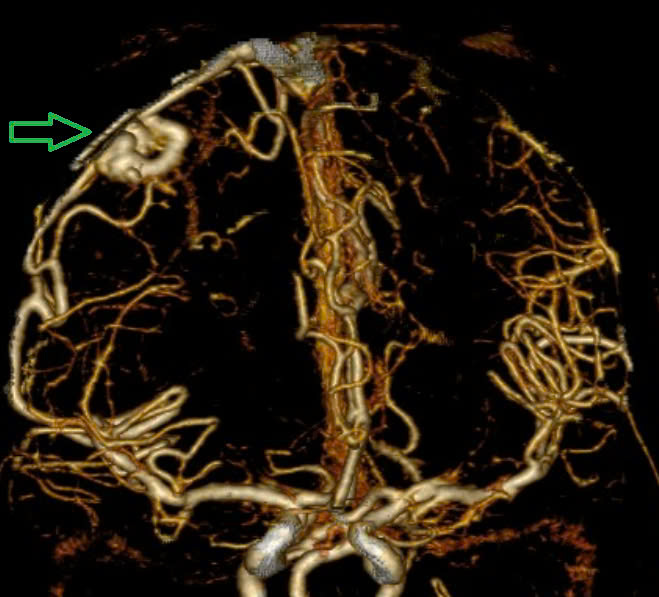

Bác sĩ cảnh báo "quả bom nổ chậm" trong não: Người trẻ dễ chủ quan với dấu hiệu này- Ảnh 1.

Hình ảnh chụp MSCT mạch não cho thấy chảy máu não thuỳ đỉnh phải, chảy máu não thất do vỡ AVM.